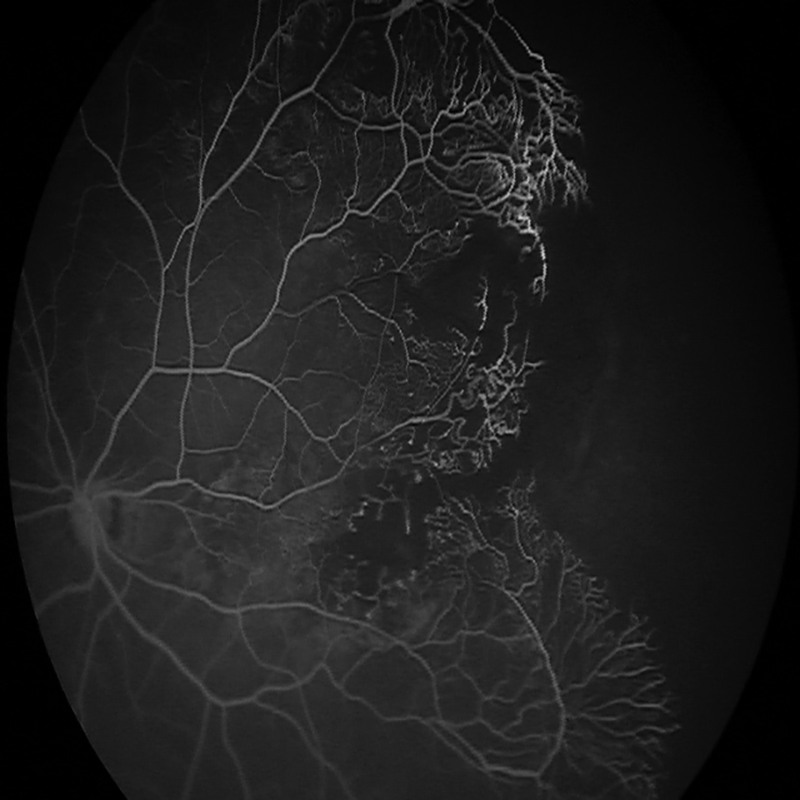

OPTOS SILVERSTONE SS OCT INDOCYANINE GREEN ANGIOGRAPHY

Η υπέρ-ευρεία, υπερ-υψηλής ανάλυσης αγγειογραφία με πράσινο της ινδοκυανίνης του OPTOS SILVERSTONE SS OCT προσφέρει την ταυτόχρονη παρατήρηση ολόκληρου του αμφιβληστροειδούς χιτώνα του οφθαλμού. Αυτό επιτρέπει την απεικόνιση ολόκληρου του αμφιβληστροειδικού αγγειακού δικτύου κατά την έγχυση της χρωστικής μέσω ανέπαφης μεθόδου.

Μπορεί να αποφέρει πρόσθετες πληροφορίες χρήσιμες στη διαφοροποίηση μεταξύ των χοριοειδικών όγκων, επιτρέποντας τον ακριβέστερο σχεδιασμό θεραπείας και παρακολούθησης.

Αυτό μας επιτρέπει να διαγνώσουμε οφθαλμική παθολογία που ίσως παρουσιαστεί πρώτα στην περιφέρεια του αμφιβληστροειδούς, με αποτέλεσμα πιο ακριβής διάγνωση για τον ασθενή.